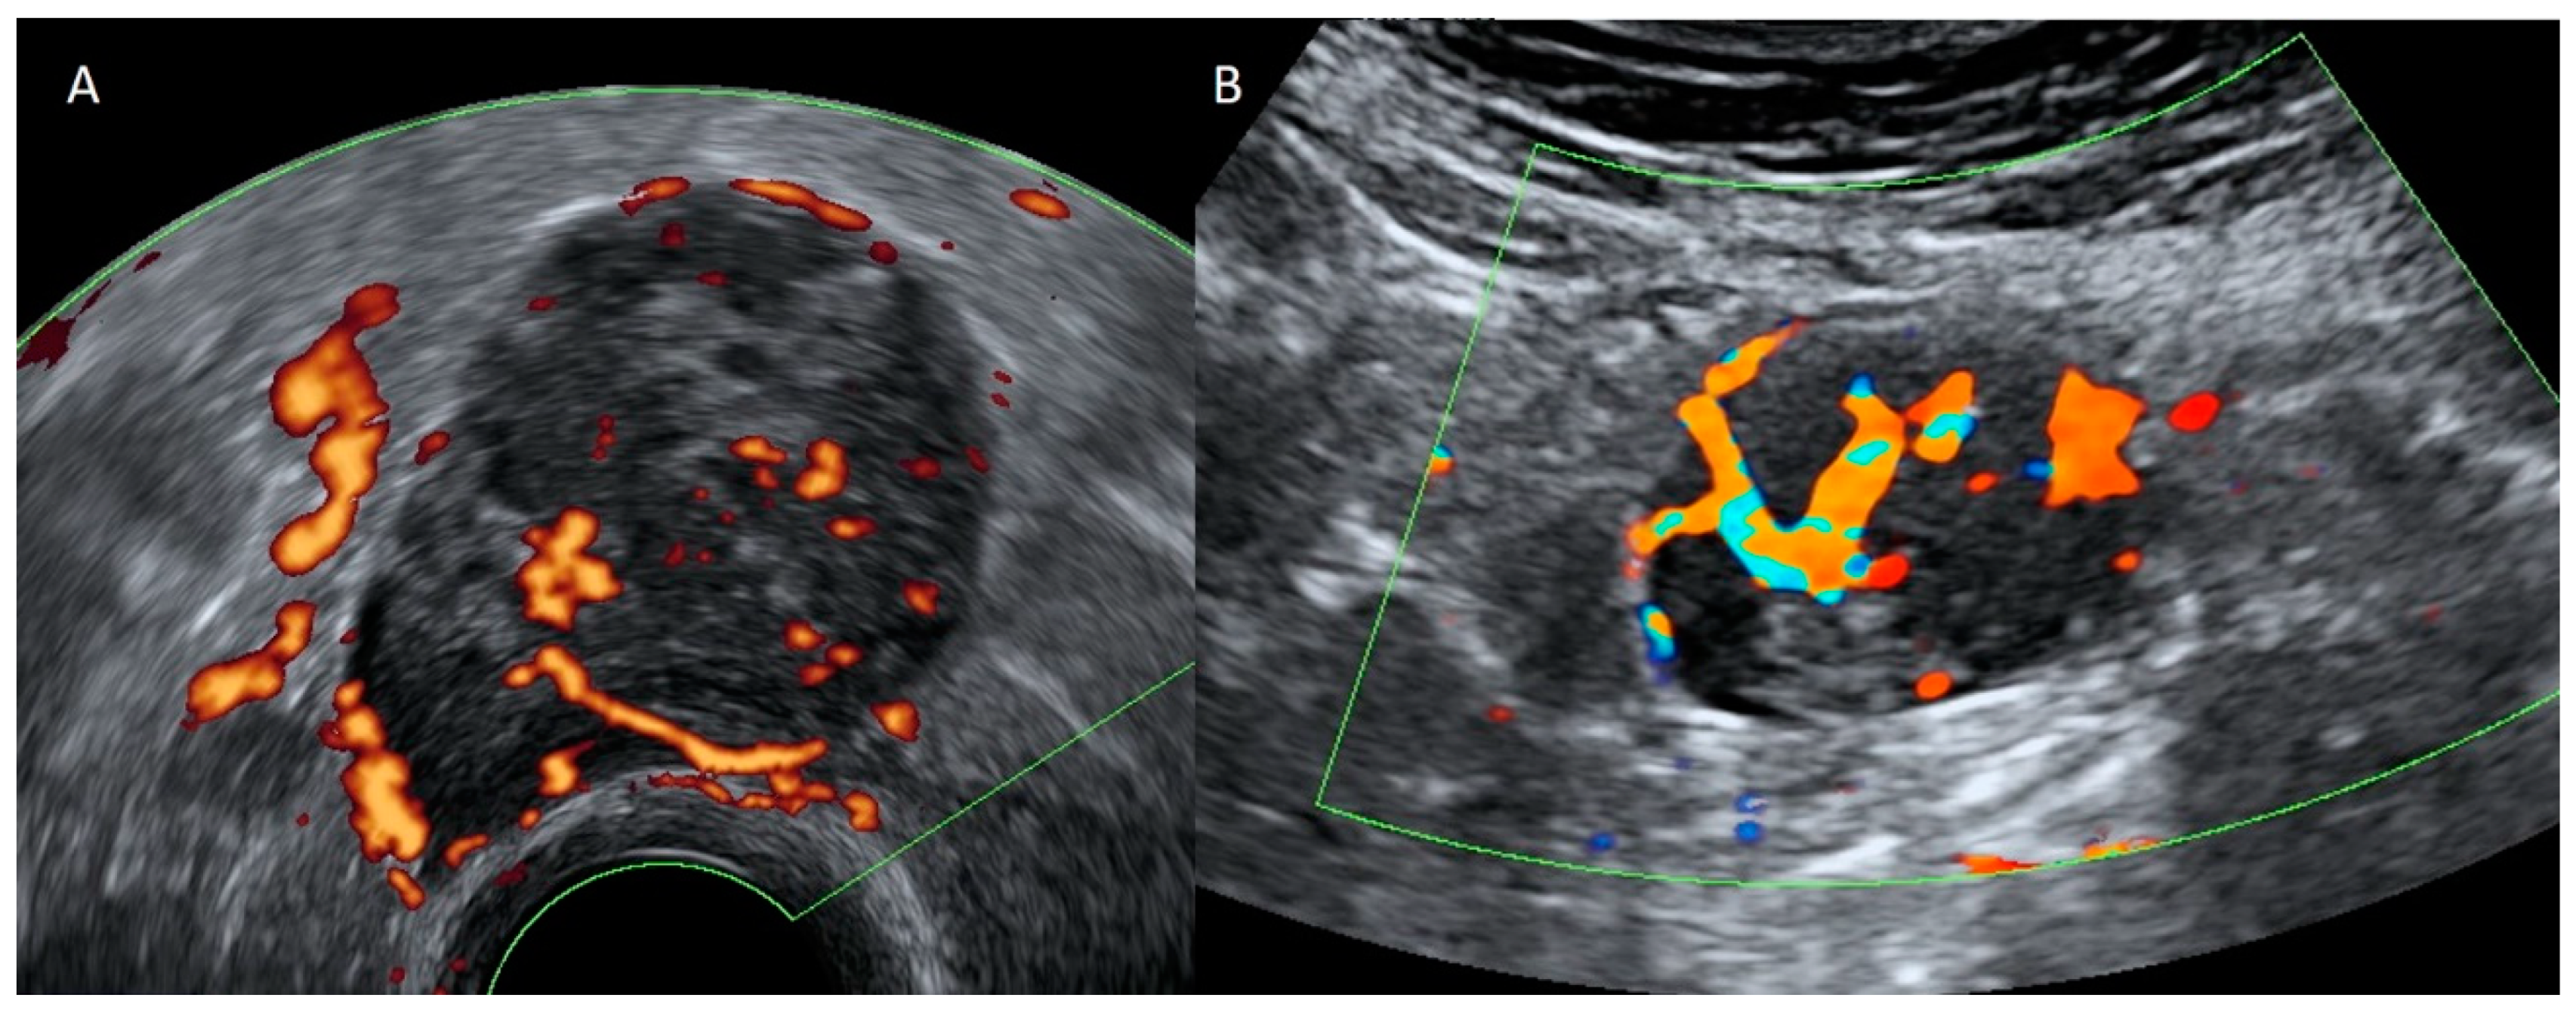

4.1. Pelvic Congestion

4.2. Thrombosis

4.3. Aneurysm